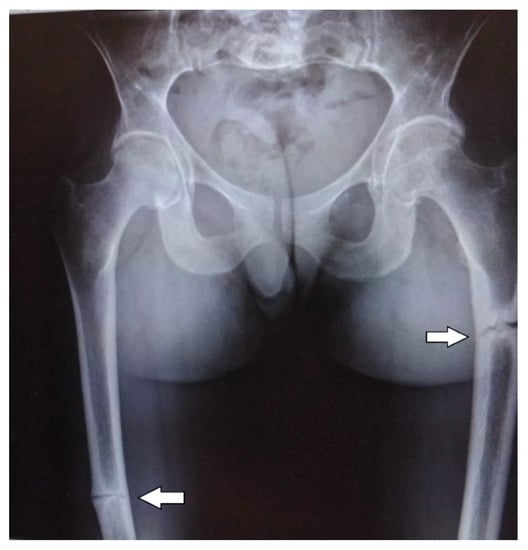

The abdominal ultrasound examinations showed the features of urolithiasis in 3/16 patients, and the X-ray examinations revealed the most common disorders of bone mineralization, abnormalities in the epiphysis of long bones–dilatation, uneven contours, bone defects, and fractures (Figure 1 and Figure 2).

Figure 2. Fractures of the femurs in an adult patient with infantile HPP.

Bone structure abnormalities observed in X-ray were characteristic and most severe for the perinatal and infantile types (they occurred in all the patients of these groups), while in other HPP types, they occurred much less frequently. A decrease in bone mineral density, assessed by densitometry, was observed in the infantile and childhood types, but it should be noted that bone demineralization was described in the perinatal type on bone radiography. In this case, DXA was not performed due to the severe patient’s condition.